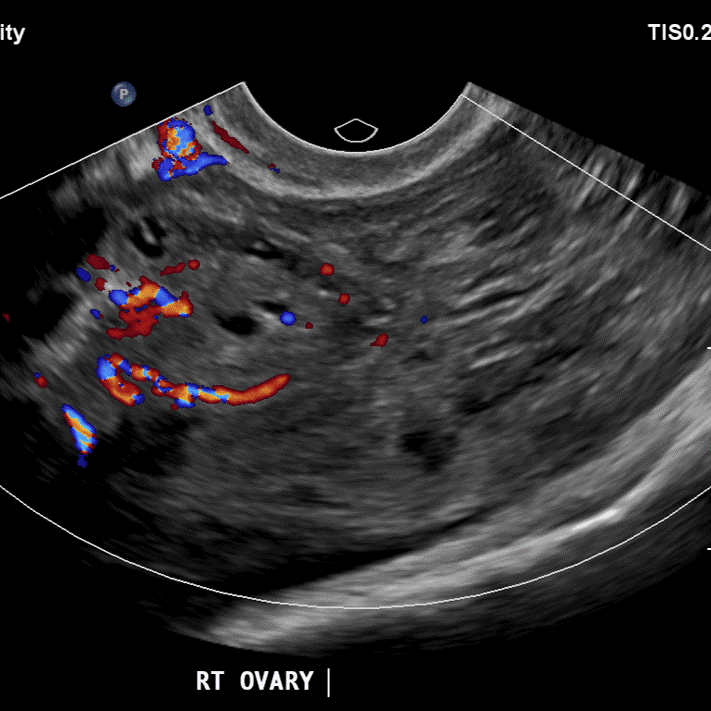

Ultrasound confirms right adnexal ruptured corpus luteum.

On Spectral analysis, easy to separate clot from the uterus. There is also a 1.9 x 1.2 cm right adnexal cyst. Ultrasound shows cyst is likely an involuting corpus luteum.

On further questioning, pain started shortly after intercourse. Patient remained uncomfortable, and was eventually taken to the OR, where a large hemoperitoneum was evacuated, and a right adnexal cyst with wall defect was confirmed.